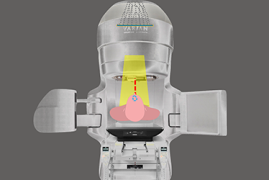

Radiocirurgia Craniana (SRS) e Radiocirurgia Estereotáxica Fracionada (SRS – fracionada)